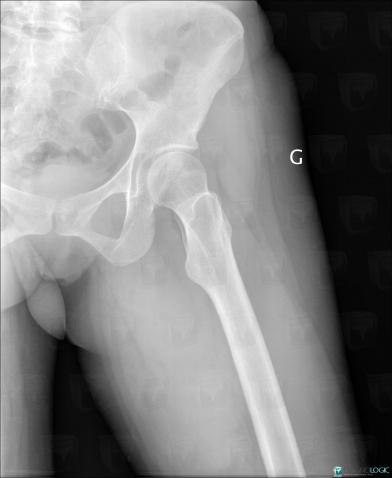

Desmoid tumor, Other soft tissues/nerves - Thigh, X rays

Here is the specific information in the key image above:

- Diagnosis Desmoid tumor, Location(s) Other soft tissues/nerves - Thigh, with gamuts